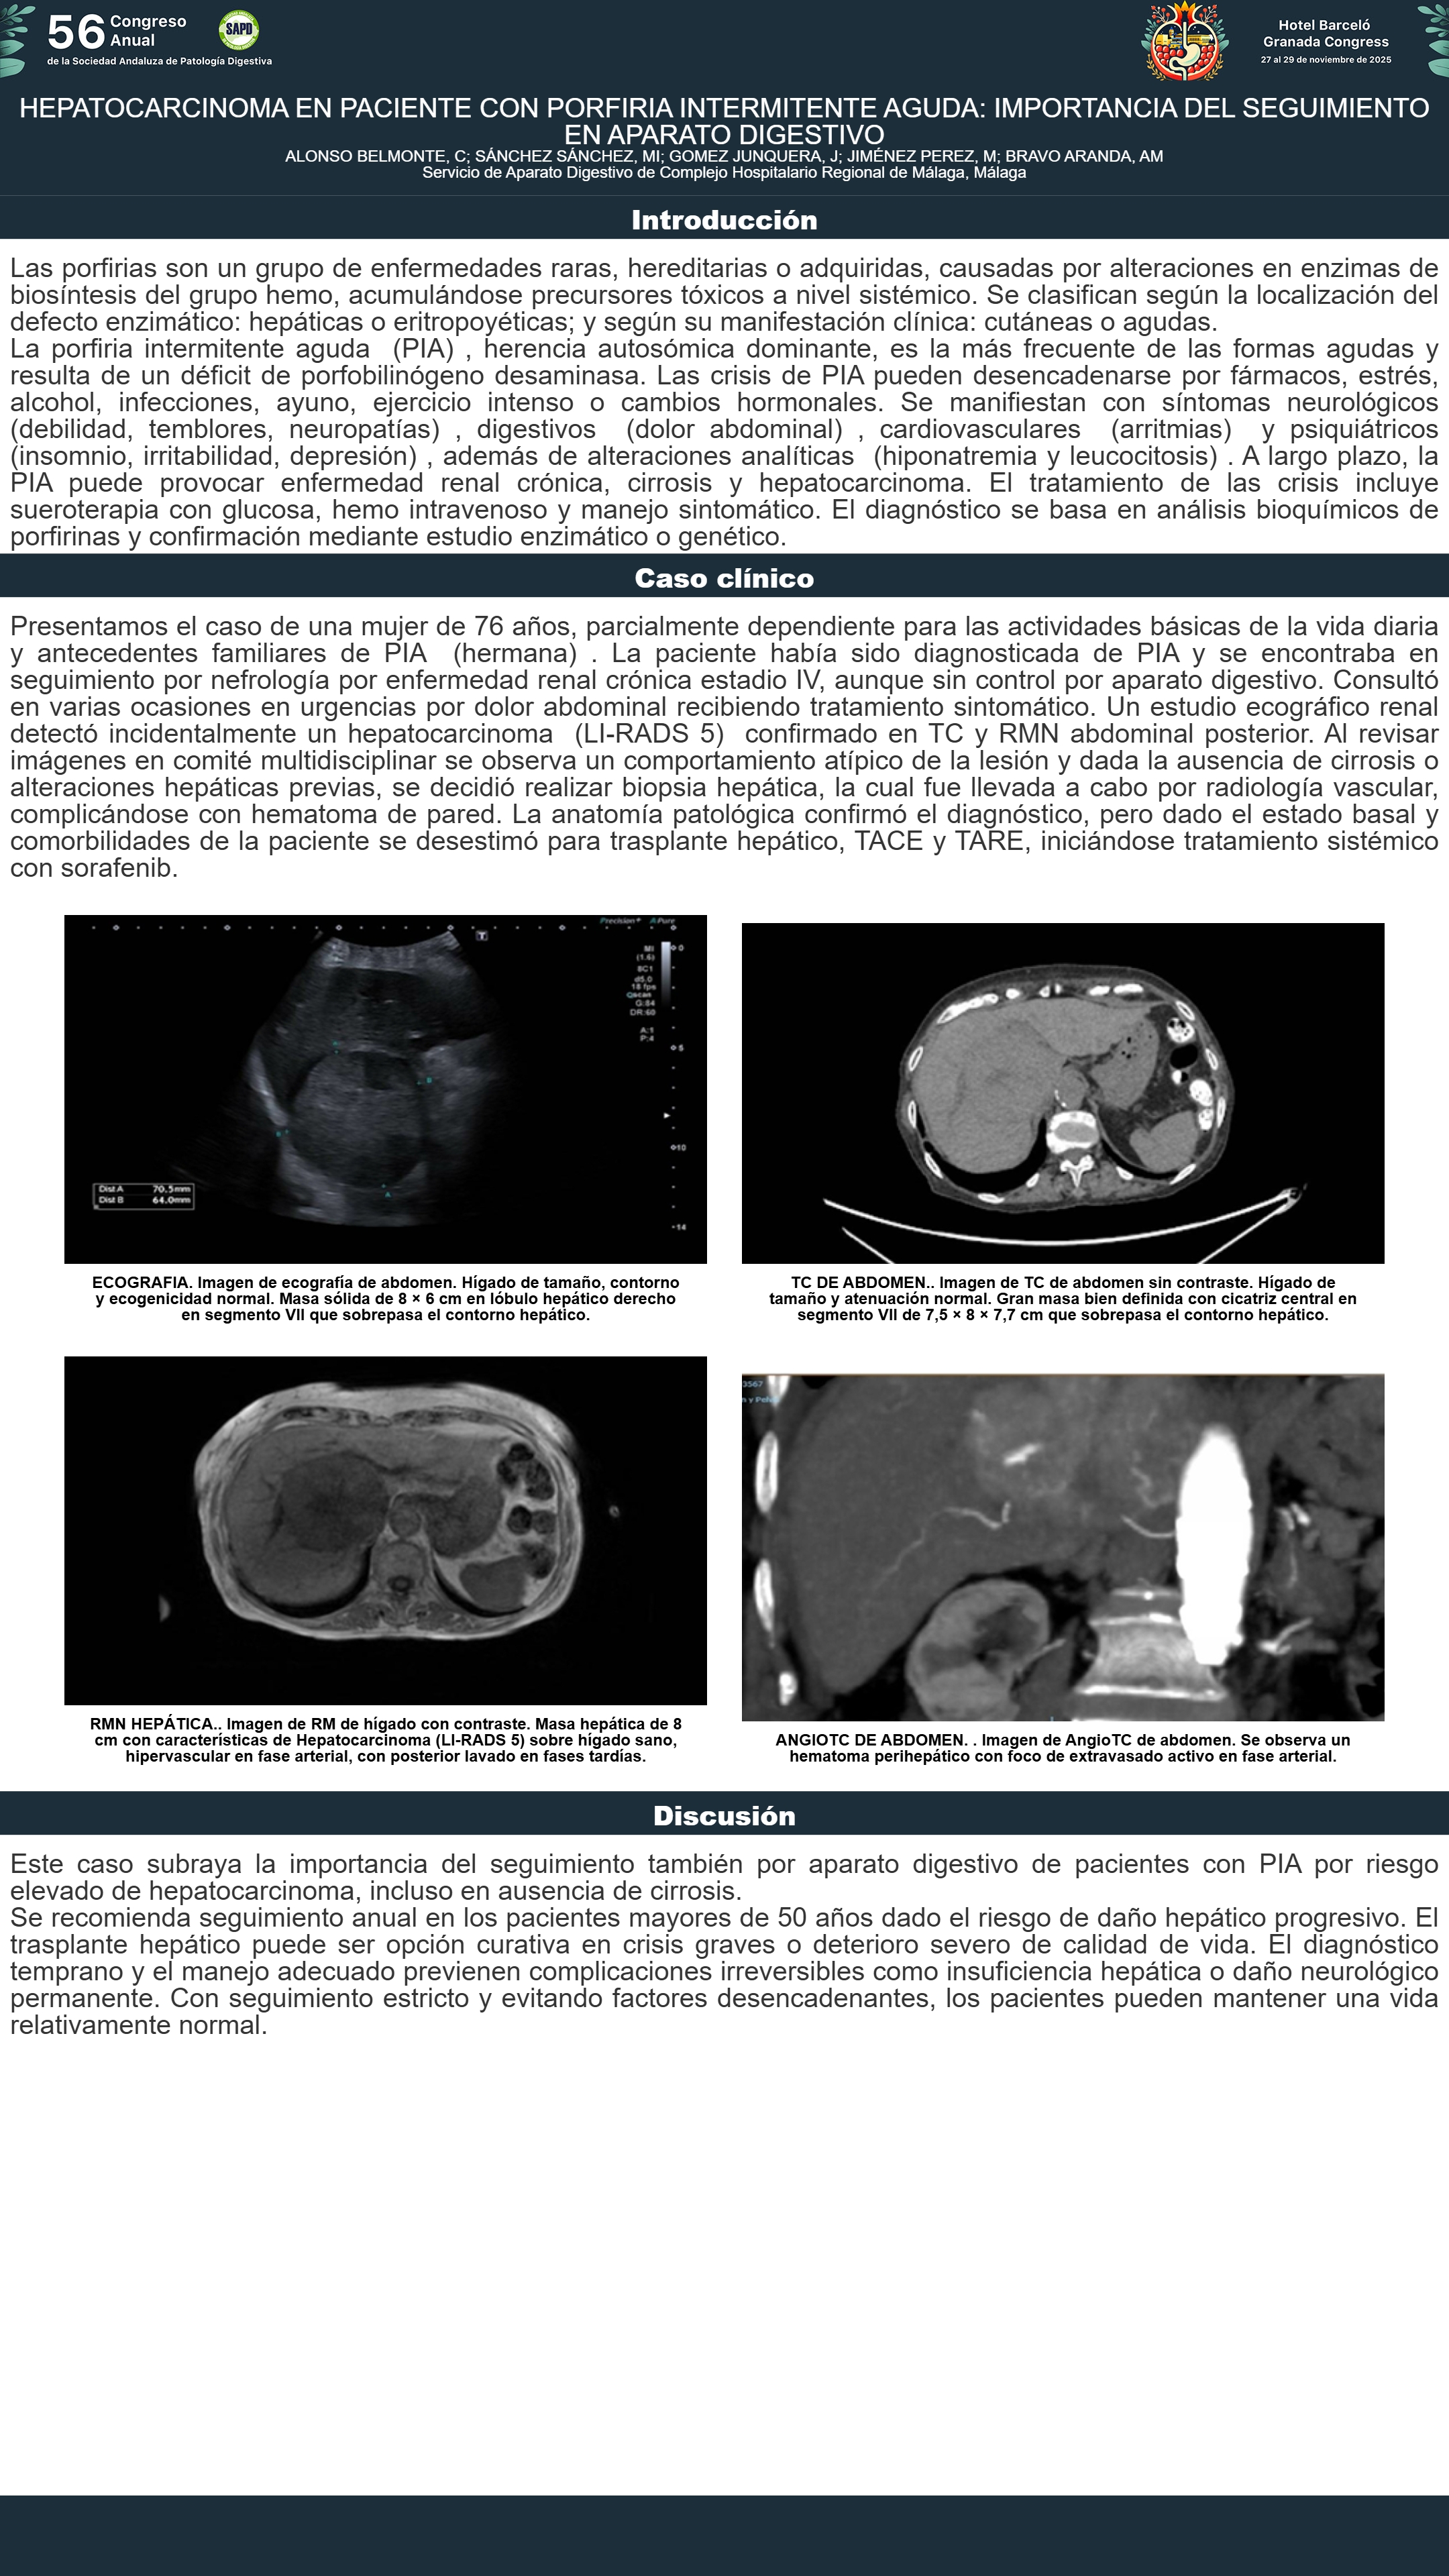

[CP-077] HEPATOCARCINOMA EN PACIENTE CON PORFIRIA INTERMITENTE AGUDA: IMPORTANCIA DEL SEGUIMIENTO EN APARATO DIGESTIVO